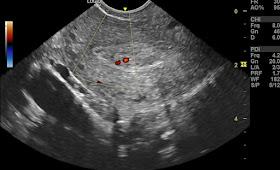

He underwent an ultrasound scan of the left kidney, which showed the following findings:

- A calculus of 10 mm in the PUJ, which is the junction between the renal pelvis and the ureter. This is also known as UPJ calculus. This calculus causes a partial obstruction of the urine flow from the kidney to the bladder, resulting in dilation of the renal pelvis and calyces. This is called hydronephrosis. The degree of hydronephrosis is moderate in this case, as the renal parenchyma is still visible and not completely compressed by the urine in the dilated pelvicalyceal system.

- Another smaller renal calculus of 4 mm in the lower pole of the kidney. This calculus does not cause any obstruction or hydronephrosis, but it may cause pain or hematuria if it moves or grows.

- Two ultrasound images and two color Doppler ultrasound images are shown below.

Ultrasound image of PUJ calculus:

Ultrasound image of lower pole calculus:

Color Doppler image of PUJ calculus with twinkle artifact:

Color Doppler image of PUJ calculus:

The ultrasound images show the cross-sectional views of the kidney, with the PUJ calculus marked by an arrow. The color Doppler images show the blood flow in the renal vessels, with the PUJ calculus producing a characteristic "twinkle" artifact. This artifact is caused by the reflection of the Doppler signal from the surface of the calculus, creating a color noise that resembles a twinkling star. This artifact helps to differentiate a calculus from other causes of acoustic shadowing, such as air or bone.